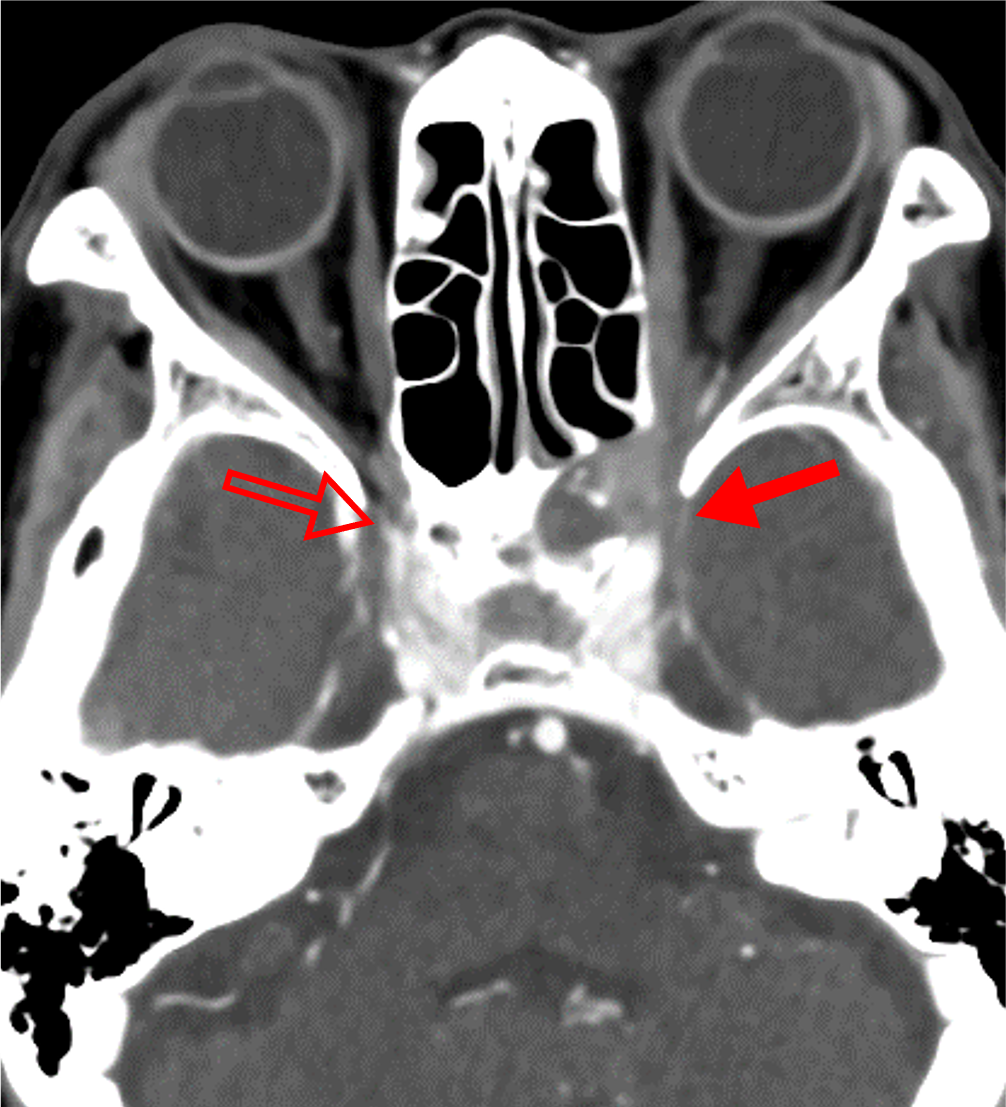

1か月前からの左眼痛、2週間前からの視野異常があり、前医で蝶形骨洞真菌症と診断された。視力障害の急速な進行と左内側視野欠損を来たしたため、当院に紹介された。造影CTにて左蝶形骨洞から左海綿静脈洞・眼窩尖部に浸潤する浸潤性真菌症を指摘された。緊急手術が施行され、病変から糸状様真菌が検出された。

急性浸潤性真菌性副鼻腔炎は臨床経過が4週間以内と急速に進行する病態を示す。骨破壊を伴って副鼻腔から眼窩・海綿静脈洞・頭蓋内に浸潤が見られる。また血管侵襲性が強く、時に仮性動脈瘤形成や動脈狭窄・閉塞、血栓形成を引き起こす。血管に沿って進展し、骨破壊を伴わずに副鼻腔外に炎症が浸潤する場合がある。

造影CTでは骨破壊の有無、副鼻腔外への炎症浸潤、また仮性動脈瘤や動脈狭窄・閉塞、血栓形成を評価する。海綿静脈洞は動脈性病変、静脈洞血栓、炎症浸潤が混在する可能性があり、早期動脈相・後期動脈相・平衡相を撮像することでこれらを鑑別する。

静脈の関与が少ない早期動脈相で動脈を評価するため、ボーラストラッキング法を用いた撮像を行う。一般的には総頚動脈や内頚動脈、中大脳動脈にROIをおいてモニタリングされることが多いが、本症例では海綿静脈洞の描出ができるだけ少ないタイミングで行うために、大動脈弓部にROIを設定した。また、海綿静脈洞の評価の際、静脈の濃染があり、炎症性組織の濃染がないタイミングでの評価を行うため、静脈相ではなく後期動脈相を撮影している。平衡相での濃染の有無で炎症性組織と静脈洞内血栓の鑑別が可能である。